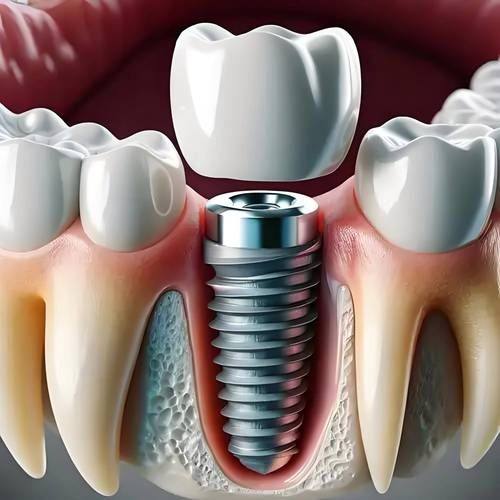

在口腔治疗中,种植牙和正畸是特别多人关注的项目。北京劲松口腔(方庄店)在这两个项目上不仅技术出众,价格也十分实惠。以下是2024年北京劲松口腔方庄店种植牙与正畸价格表:

| 种植牙 | 韩国登腾种植牙 | 4980元/颗起 |

| 美国皓圣种植牙 | 6980元/颗起 | |

| 瑞士ITI种植牙 | 12800元/颗起 | |

这样的价格在同行业中具有较大的竞争力,而且北京劲松口腔(方庄店)采用的都是精良的技术和优质的材料,让患者花小钱办大事。

宣立国医生,从事口腔临床工作多年,在种植牙领域有着丰富的经验和深厚的技术功底。他擅长各种复杂种植牙手术,能够根据患者的具体情况制定个性化的种植方案,让患者重新拥有健康的牙齿。

从医生方面来看,前面我们已经介绍了北京劲松口腔(方庄店)的医生团队,他们不仅专精技术实力强,而且临床经验多。在种牙过程中,医生会进行详细的口腔检查和评估,制定科学合理的种植方案,确保种牙的成功几率和成效。